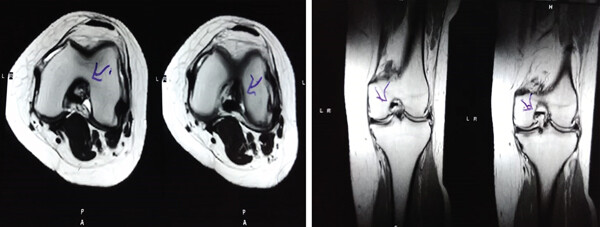

MRI:治療前后的MRI結果

治療前 MRI 顯示內側和外側半月板后角 III 級撕裂。

治療后MRI檢查顯示內側和外側半月板后角撕裂有所改善。患者癥狀改善,日常生活活動能力增強。

結論:間充質干細胞治療后,MRI檢查顯示內側和外側半月板后角撕裂有所改善 ,關節功能也有改善,未出現嚴重不良事件。可以達到干細胞治療半月板損傷短期療效的目標。